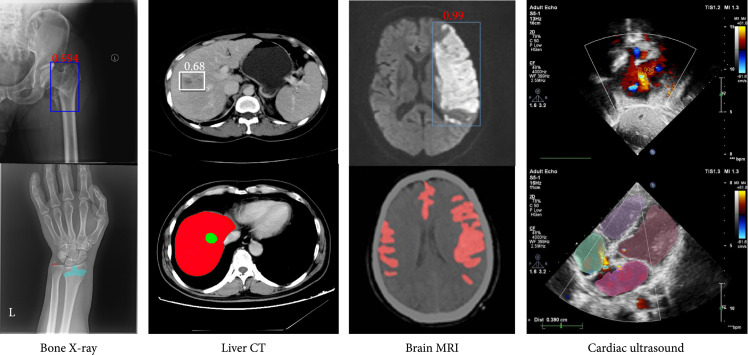

重要性随着人工智能(AI)的蓬勃发展,特别是深度学习的最新进展,利用先进的基于深度学习的方法进行医学图像分析已成为医学界和学术界的一个活跃研究领域。本文综述了深度学习在医学图像分析和临床应用方面的研究进展。它还讨论了该领域存在的问题,并提供了可能的解决方案和未来的方向。亮点。本文综述了卷积神经网络技术在临床应用中的进展。更具体地说,最先进的临床应用包括四个主要的人体系统:神经系统、心血管系统、消化系统和骨骼系统。总体而言,根据现有的最佳证据,深度学习模型在医学图像分析中表现良好,但不可忽视的是,来自小规模医学数据集的算法阻碍了临床应用。未来的方向可能包括联合学习、基准数据集收集和利用领域主题知识作为先验。结论最近先进的深度学习技术在医学图像分析中取得了巨大成功,具有高精度、高效率、稳定性和可扩展性。技术进步可以缓解对高质量大规模数据集的高需求,这可能是该领域未来的发展之一。

Importance. With the booming growth of artificial intelligence (AI), especially the recent advancements of deep learning, utilizing advanced deep learning-based methods for medical image analysis has become an active research area both in medical industry and academia. This paper reviewed the recent progress of deep learning research in medical image analysis and clinical applications. It also discussed the existing problems in the field and provided possible solutions and future directions.Highlights. This paper reviewed the advancement of convolutional neural network-based techniques in clinical applications. More specifically, state-of-the-art clinical applications include four major human body systems: the nervous system, the cardiovascular system, the digestive system, and the skeletal system. Overall, according to the best available evidence, deep learning models performed well in medical image analysis, but what cannot be ignored are the algorithms derived from small-scale medical datasets impeding the clinical applicability. Future direction could include federated learning, benchmark dataset collection, and utilizing domain subject knowledge as priors.Conclusion. Recent advanced deep learning technologies have achieved great success in medical image analysis with high accuracy, efficiency, stability, and scalability. Technological advancements that can alleviate the high demands on high-quality large-scale datasets could be one of the future developments in this area.